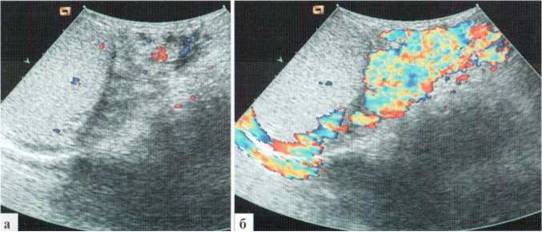

Возможной сложностью визуализации кровотока в венах гроздьевидного сплетения может оказаться его низкая скорость при выраженных степенях варикоцеле: в покое практически не происходит допплеровского окрашивания дилатированных вариксов, и кровоток достоверно может быть зафиксирован только при пробе Вальсальвы (рис. 3.7).

Рис. 3.07. Особенности допплеровской визуализации кровотока в резко дилатированных венах гроздьевидного сплетения: а —в В-режиме определяется выраженное расширение и резкая извитость вен гроздьевидного сплетения; б — ДДС: в покое (клиностаз) в венах гроздьевидного сплетения практически не определяется движение крови, кровоток в яичке сохранен; в — ДДС: проба Вальсальвы. Определяется резкое повышение интенсивности сосудистого рисунка, что связано с повышением скорости кровотока в венах гроздьевидного сплетения. Примечательно, что интенсивность сосудистого рисунка в паренхиме яичка не меняется.

Как уже было отмечено, количественный анализ кровотока в венах гроздьевидного сплетения не имеет принципиального значения: всю необходимую информацию дает качественный анализ кровотока при цветовом допплеровском исследовании: изменение спектра окрашивания и резкое повышение интенсивности окрашивания при пробе Вальсальвы. Кроме того, выполняя пробу Вальсальвы, дети всегда резко напрягают живот, что сопровождается движением всего тела и смещением поискового объема с выбранного сосуда. То есть, попытку выполнения допплерографического исследования обычно приходится предпринимать несколько раз.

При успешной фиксации спектра кровотока определяется изменение его направления, продолжающееся несколько секунд (рис. 3.8). Скорость кровотока в варикозно расширенных венах гроздьевидного сплетения в состоянии покоя в клиностазе может быть минимальной и практически не фиксироваться (см. рис. 3.7), а при пробе Вальсальвы — достигать 10—20 см/сек.